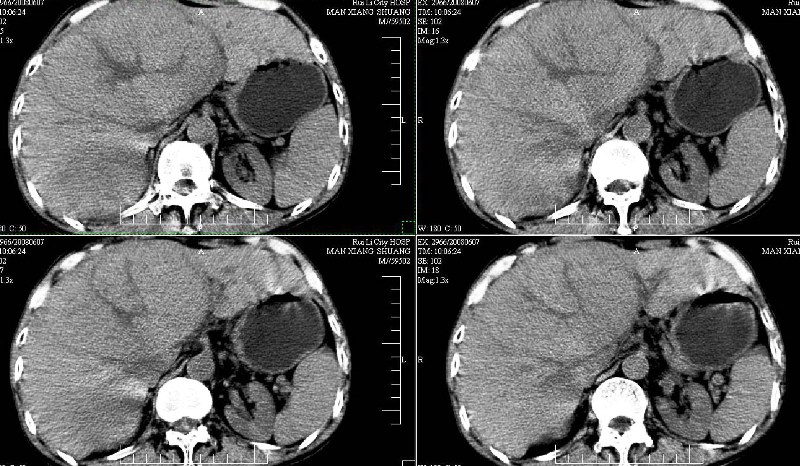

标题: CT13937:M,42A.腰疼一周。

ct(椎间盘扫描):椎间盘炎,建议dr。

dr:l4骨质破坏,转移可能。

胸部摄片未见异常。临床医生体检发现上腹部饱满。

ct:肝癌腰椎转移。临床医生:肝脏、骨转移,肿瘤来自?前列腺?!

建议强化观察肝内病灶特点,考虑肝癌骨转移。

支持肝癌伴椎体转移瘤。腹膜后建议ct增强,好象有增大的淋巴结。

1、支持肝癌肝内及腰椎转移。

2、肝脏内好象有多个病灶,建议增强检查。

3、前列腺好象还可以,不过图像看得不太清。